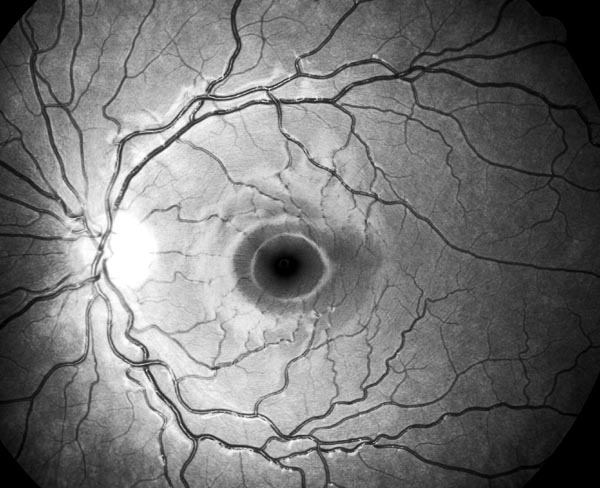

Oftalmo-neurologická diagnostika 1956, Michelem popsaný obraz si můžeme kdykoliv vyvolat, vyšetřujeme-li oční pozadí podle Vogtova návrhu bezčerveným světlem.

The temporal raphe of the human retina Amer.J.ophthal. 62:926/1966, popsal předěl ve vrstvě nervových vláken temporálně od makuly mezi horní a dolní polovinou sítnice.